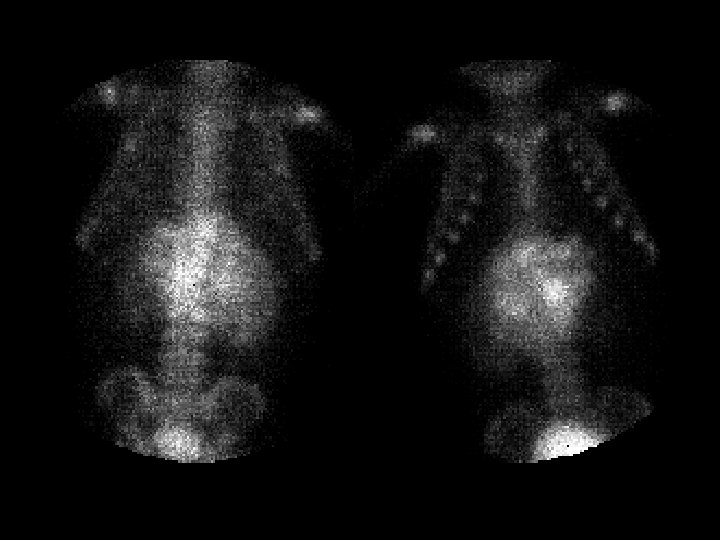

Osteopetrosis Tc99 m sulfur colloid i v intense

Osteopetrosis • • • Tc-99 m sulfur colloid, i. v. intense liver/spleen uptake, little or none in the bone marrow Trabecular --> compact bone --> Diffuse inc bone density Anemia w/extramedullary hematopoiesis ddx: (adults) – – – myelofibrosis sclerotic metastases renal osteodystrophy multiple myeloma Paget’s